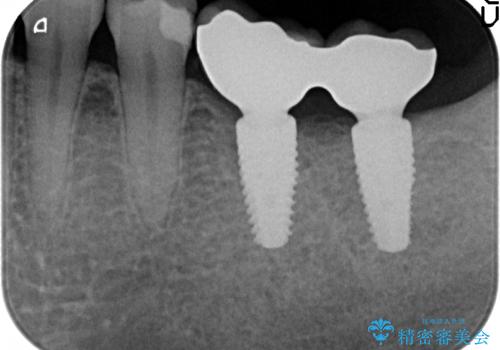

- 左下奥歯の銀歯を白くしたいと来院された方の症例です。

銀歯を除去後、セラミックインレーによる修復を行いました。